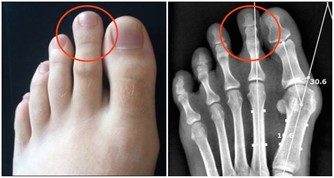

當身體缺乏維生素會容易使許多慢性疾病找上門來,若是缺乏了維生素C,那麼就會抑制血液的正常流動,也會容易使身體出現壞血病或者是牙齦出血若是缺乏維生素D那麼會加速鈣元素的流失,不利於關節和骨骼的健康。

維生素A又名視黃醇,可以抗干眼病因子,

當人體一次性接受 對於兒童來說,